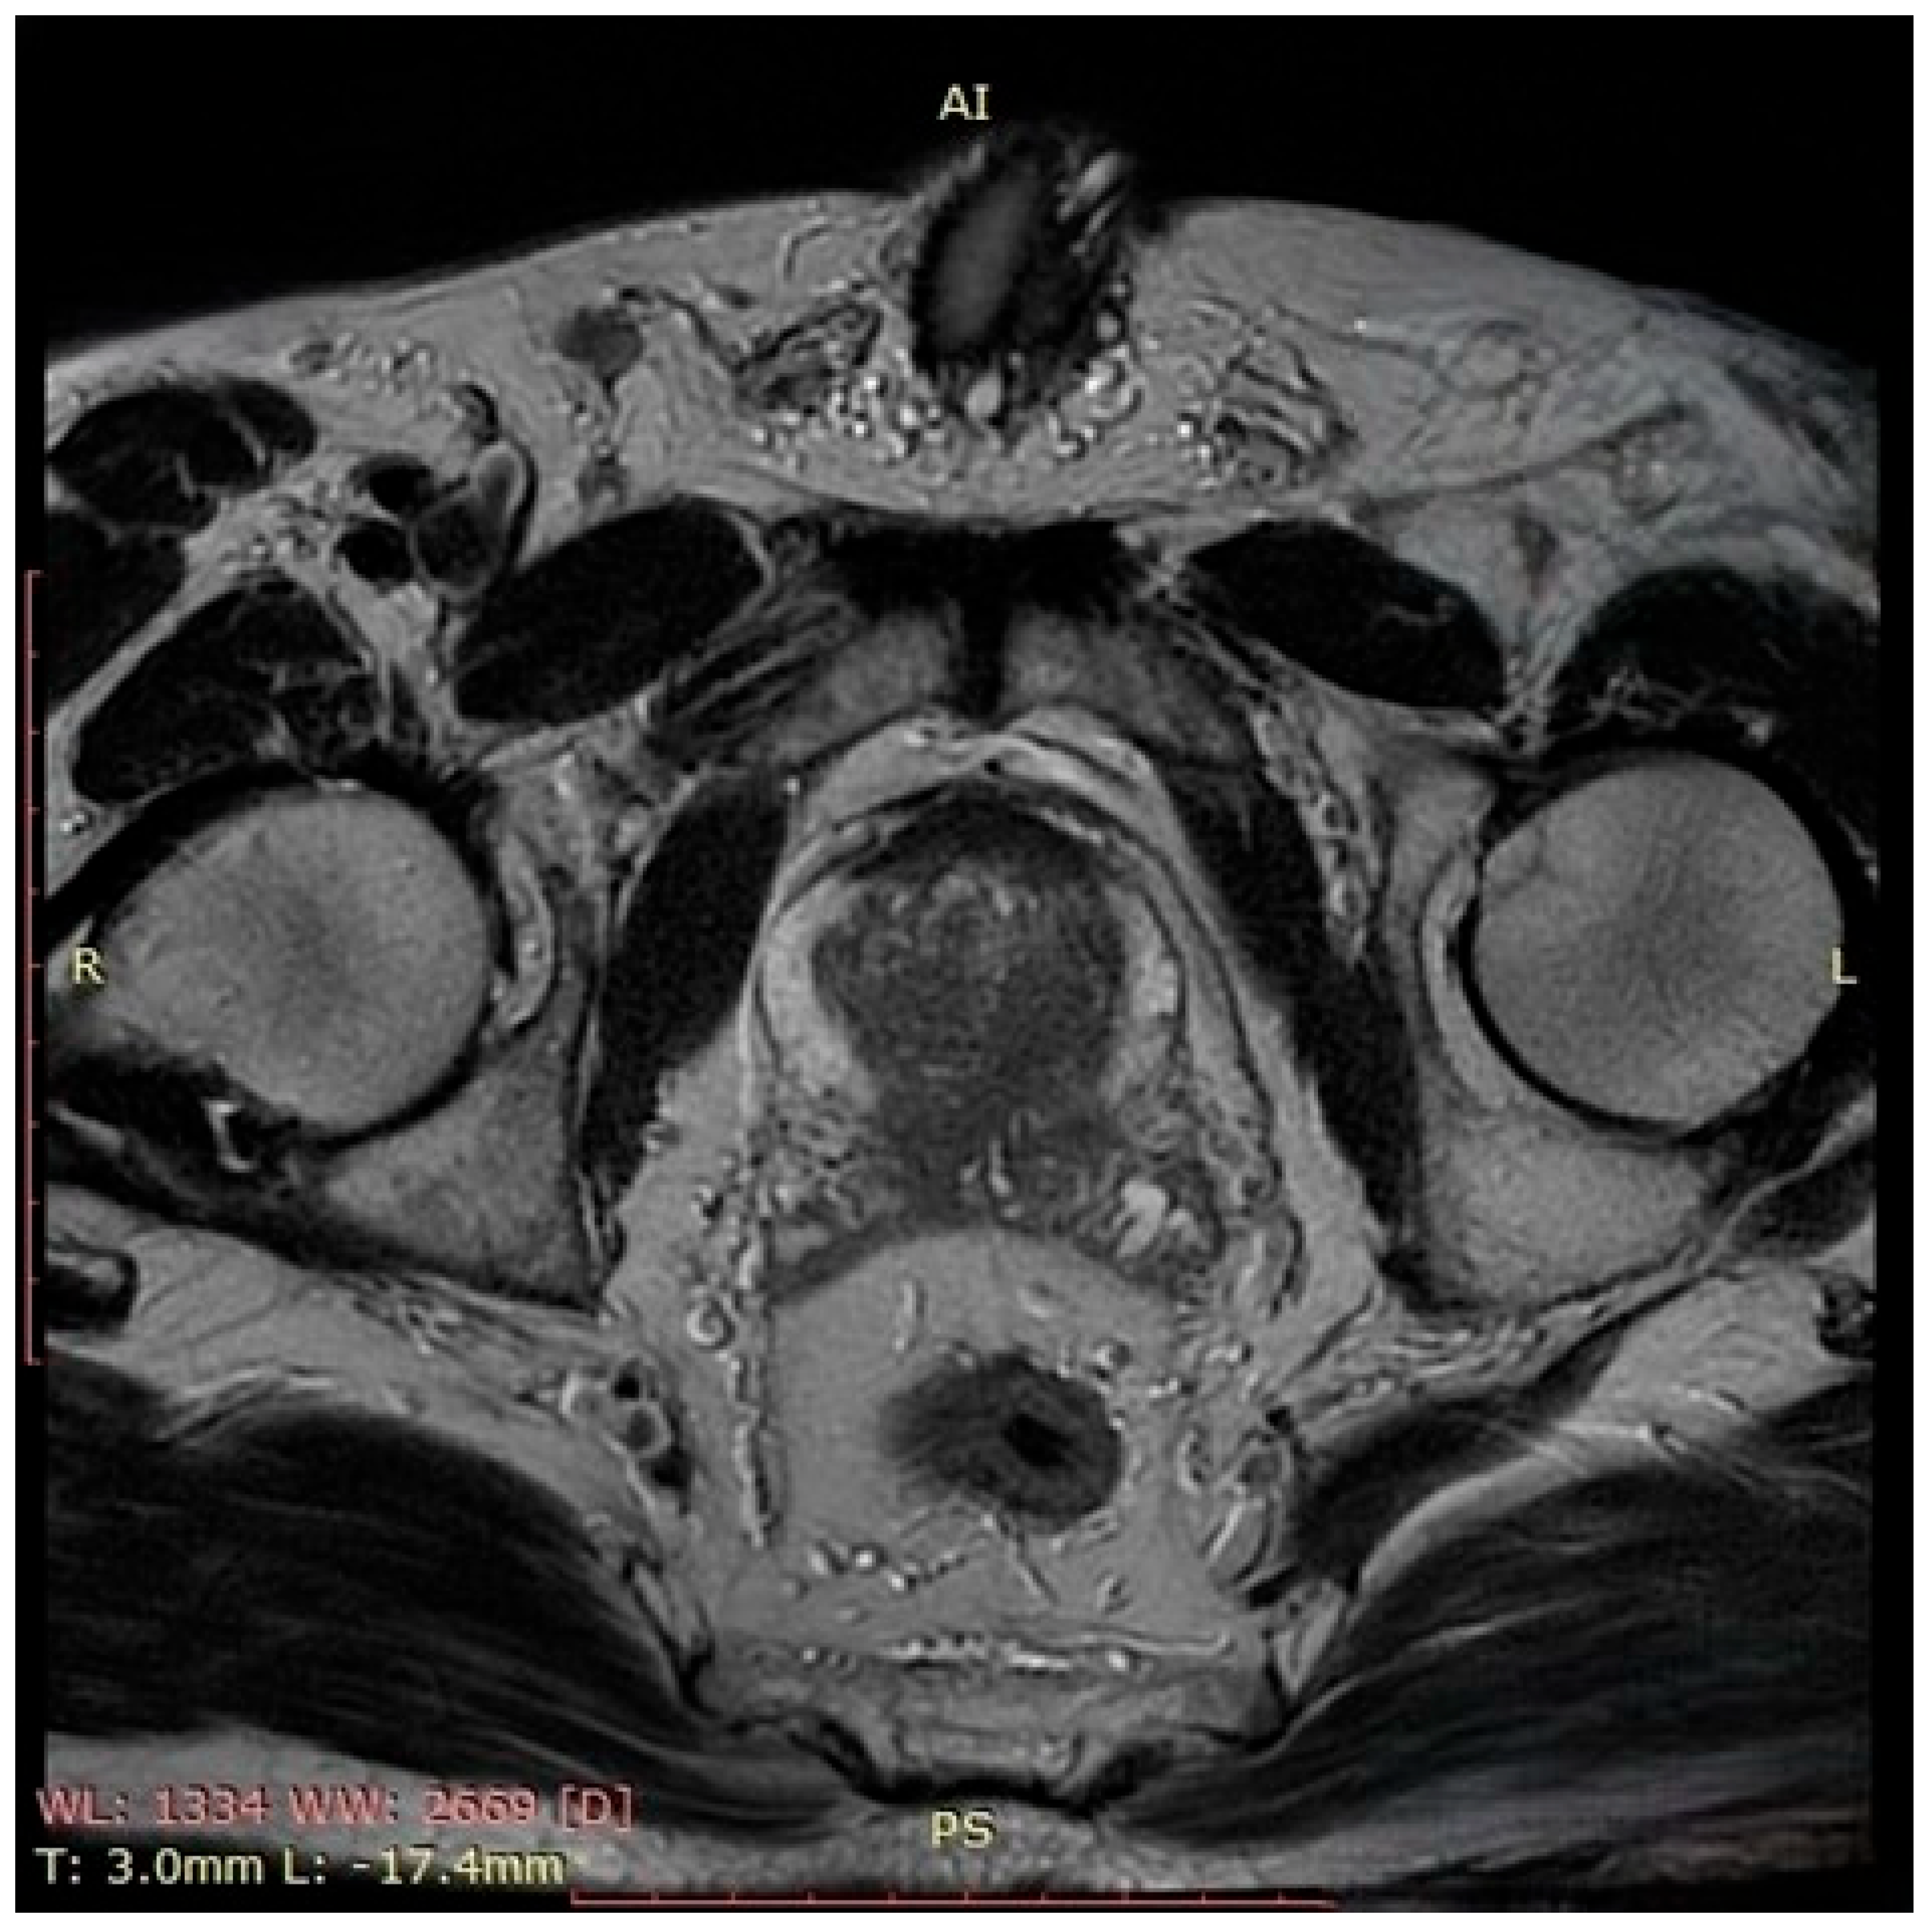

In October 2023, the patient presented with complete urinary retention and an indwelling urethrovesical catheter in place. A thoraco-abdomino-pelvic staging CT scan identified two pulmonary nodules and multiple cervico-thoraco-abdomino-pelvic lymph nodes without any sign of active hematological disease. A PET-CT scan performed at that time showed multiple bilateral latero-cervical lymph nodes, without evidence of significant diffuse 18F-FDG uptake. Unfortunately, despite our efforts, we were unable to retrieve the original imaging files or the formal radiology report. The patient exhibited no systemic symptoms such as night sweats, fatigue, fever, or weight loss and remained active. His medication regimen included ibrutinib for non-Hodgkin lymphoma, Perindopril for grade I hypertension, Omeprazole as a gastroprotective agent, and Allopurinol for high uric acid levels. The patient was a non-smoker and non-drinker without any family history of autoimmune disorders or cancers, including prostate cancer. The patient’s ECOG performance status grade was also 0, but the MIPI score was 3.47 points, still indicating an intermediate-risk category with a median overall survival of approximately 51 months. Given the patient’s clinical–biological status and considering the risks and limitation of prostate cancer screening, the decision was to measure the PSA level. Following two consecutive measurements of the Prostate-Specific Antigen level that showed elevated levels (11.7 ng/mL), multiparametric prostate Magnetic Resonance Imaging (MRI) (Figure 1) was performed. The prostate MRI demonstrated a bilateral ill-defined lesion in the peripheral zone, with Prostate Imaging Reporting and Data System (PIRADS) 5 characteristics, highly suggestive of malignancy. Considering the laboratory and imaging investigations, MRI fusion-guided transrectal prostate biopsy was indicated and performed. The histopathological findings described secondary prostatic lymphoma.

Figure 1.

This axial T2-weighted image of the prostate demonstrates a hypointense lesion located in the peripheral zone, bilaterally, which is ill-defined, with disruption of the normal high-signal intensity of the peripheral zone and focal capsular bulging. There is no clear evidence of extracapsular extension or seminal vesicle invasion. These findings are suggestive of a PIRADS 5 lesion and highly suspicious for clinically significant prostate cancer.